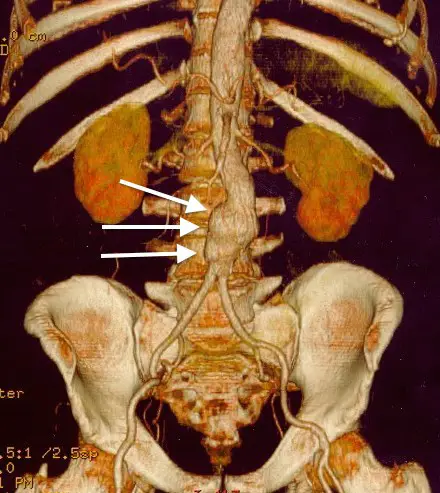

Abdominal Aortic Aneurysm

Abdominal aortic aneurysm (AAA) is an aneurysm of the abdominal aorta.

Abdominal aortic aneurysm typically develops above the aortic bifurcation but below the renal arteries.

Abdominal aortic aneurysm (AAA) is typically associated with hypertension and atherosclerosis.

Atherosclerosis causes the vessel wall to atrophy and become weaker by raising the diffusion barrier to the media.

Complications of abdominal aortic aneurysm (AAA) include:

- Rupture, especially when the diameter is greater than 5 cm